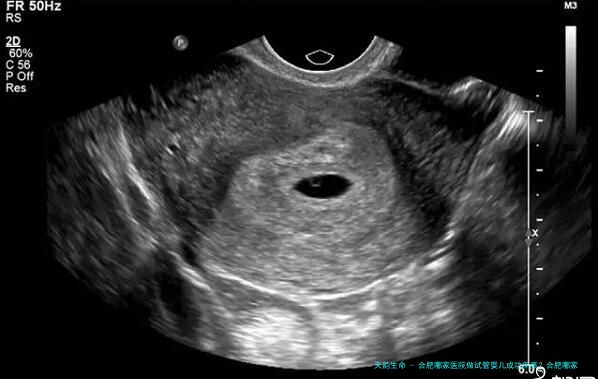

5、出现两个胎心:在怀孕两三个月左右去医院拍B超的时候如果出现了两个胎心,那么恭喜你了,怀上了双胞胎。

在怀孕期间如果出现上面这些症状那么代表怀了双胞胎,但每个人的身体情况不同,所表现得症状不同,大家可以在做孕检的时候看是否能够看到两个孕囊,而且如果是双胞胎医生一般会告诉的,因为怀双胞胎的风险比单胎大,所以注意的事项也比较多,提前告知加以预防,但并不会告知是不是怀的龙凤胎,毕竟属于违法行为。